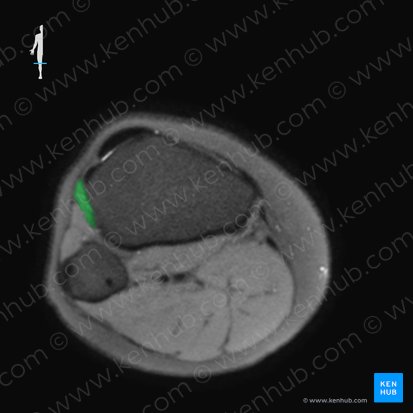

Zusammen mit den Mm. extensor hallucis longus und extensor digitorum longus befindet er sich in der Extensorenloge; dort liegt er am weitesten medial von den drei Muskeln. Die bindegewebige Hülle, die sie umschließt, verhindert eine Verlagerung der Muskeln und stellt eine natürliche Barriere für Erreger dar.

Die Extensorenloge wird durch die A. tibialis anterior versorgt, welche aus der A. poplitea dorsal des M. popliteus abgeht. In der Nähe mit dem die Extensoren versorgenden N. fibularis profundus (L4-L5) zieht diese Arterie von dorsal nach ventral durch die Membrana interossea cruris. Sie verläuft zwischen den Mm. tibialis anterior und extensor hallucis longus nach distal.